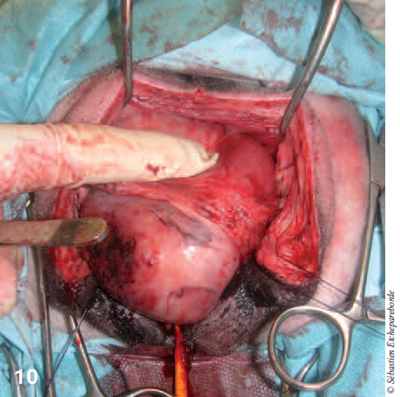

Le vagin peut ainsi continuer à être disséqué en gardant une marge de tissu autour du méat urinaire (photo 10).

photo 10

Photo 10 – La dissection du vagin est continuée par cet abord.